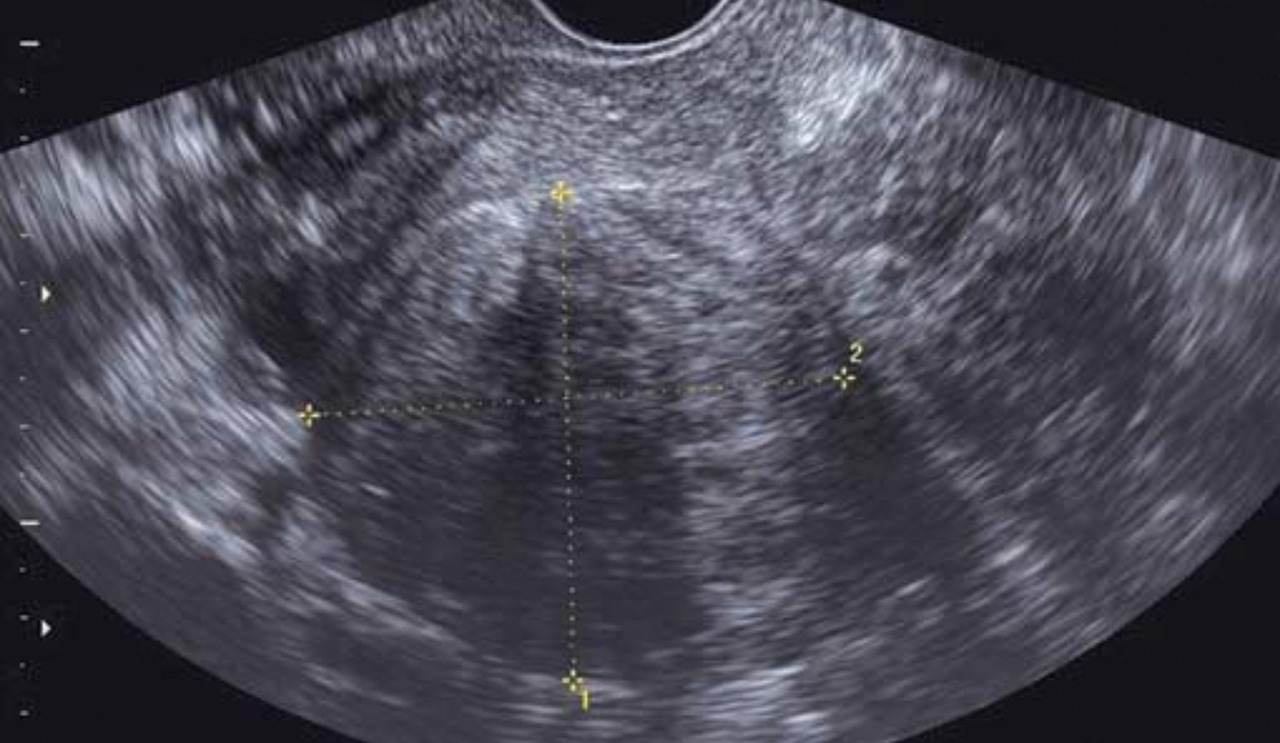

Elle est utile à l’étude du myomètre, diagnostiquant fibromes (et leur cartographie) et adénomyose (fig. 2).

Elle permet le diagnostic des pathologies intra­cavitaires (telles que polypes endo-utérins et fibromes utérins), la mesure de l’épaisseur endométriale et apprécie la régularité de l’endomètre (cancer de l’endomètre).

Une échographie pelvienne est réalisée pour confirmer le diagnostic clinique et pour apprécier le volume utérin qui peut avoir des contours déformés par les léiomyomes. Les fibromes ont un aspect échographique caractéristique, arrondi, légèrement hypo­échogène par rapport au myomètre, avec vascularisation périphérique (fig. 5). L’échographie permet la cartographie des fibromes ainsi que le suivi de leur évolution.

L’adénomyose est une infiltration du myomètre, à partir de la cavité utérine, par des glandes endométriales. Typiquement, il s’agit d’une pathologie de la quarantaine chez une multipare. Les ménométrorragies sont souvent associées à des dysménorrhées sévères de fin de règles. Le toucher vaginal retrouve un utérus augmenté de volume de façon régulière, dur, lourd et sensible à la palpation. L’échographie permet d’évoquer le diagnostic en retrouvant un utérus augmenté de volume de façon assez diffuse avec souvent une disparité de taille entre le mur antérieur et le mur postérieur. Le myomètre apparaît hétérogène mais sans noyau myomateux nettement individualisable en son sein ; on peut aussi retrouver des images kystiques myométriales et des travées hyperéchogènes.